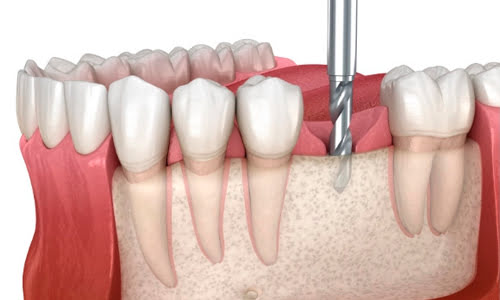

Implant Placement

This is a course that is dedicated for newcomers to implant dentistry. The curriculum is designed to provide dentists with an essential understanding of implant placement and bone grafting procedures. The details of the course include lectures, workshops, and live demonstrations involving a surgery. Dentists work with various models where they can experiment with surgical techniques.

Dental Implant

Hands-on dental implant training is provided to dentists to provide them with the essential fundamentals in providing successful implant procedures. This course is centered for dentists who are relatively unfamiliar to dental implant procedures. The core curriculum is provided through a combination of lectures, workshops, and live demonstrations. Dentists will learn surgical techniques such as atraumatic extractions, socket grafting, membranes, and implant procedures.